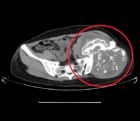

活檢

骨盆癌對骨盆腫瘤的活檢遵循骨與軟組織腫瘤活檢的一般原則。由於絕大多數骨盆手術切口經過髂嵴,因此沿髂嵴進行活檢最安全。對於發生於骨盆區的腫瘤大部分可行穿刺活檢,若腫瘤較小、位置深在或位於比較複雜的解剖部位(如骶骨前側、髂骨深部)可在CT引導下活檢。

無論採用穿刺活檢還是切開活檢,均應避免污染腹膜後間隙。由於軟骨肉瘤對放療和化療均不敏感,並且如果活檢造成局部污染,則依靠手術切除達到腫瘤的局部控制非常困難,因此對骨盆軟骨肉瘤施行活檢的技術要求非常高。

MRI

非常有助於判斷腫瘤的範圍和對輔助治療的反應。由於MRI可以顯示腫瘤三維六個方向上的範圍,因此可以用於計畫各個方向上的切除邊界,即MRI可以顯示腫瘤在遠、近、內、外、前、後各個方向上的範圍,並以此為依據計畫各方向上相應的切除邊界,發現最困難的切除部位,完善術前準備。